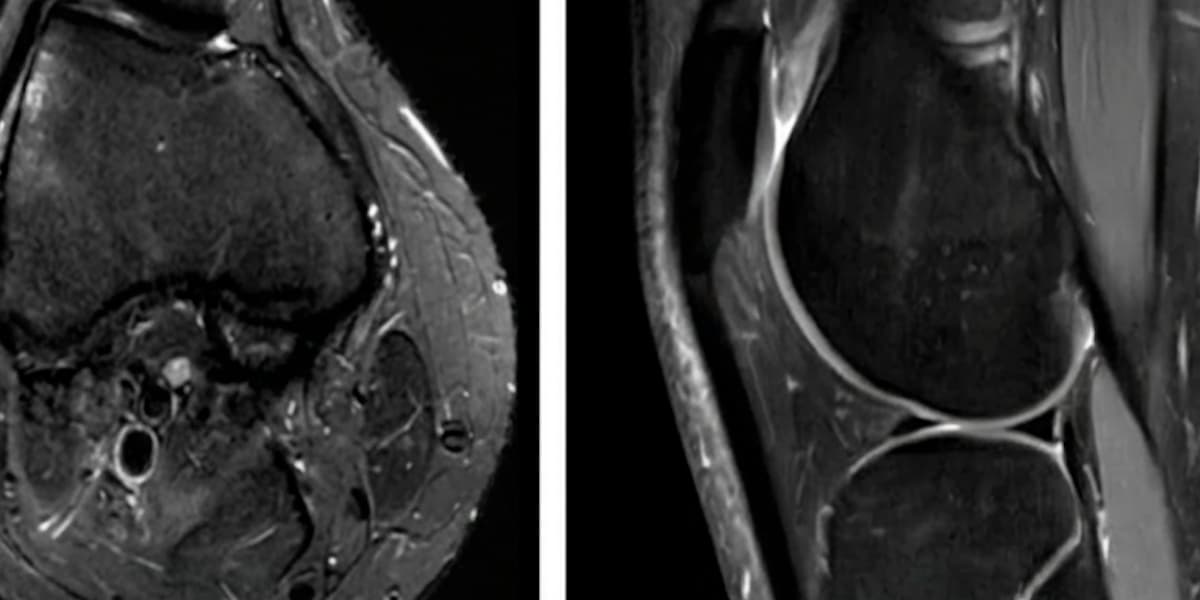

Use this blog as a trusted resource for up-to-date information on orthopedic and sports medicine news and insights. As a board-certified sports medicine surgeon specializing in complex knee conditions, such as patellofemoral instability, cartilage repair, and ACL injuries, I share the latest advancements in surgical techniques, non-operative treatments, and rehabilitation strategies. Whether you’re an athlete, an active individual, or simply seeking to understand common orthopedic issues, explore our articles to gain sports medicine news and expert perspectives, empowering your journey to recovery and optimal mobility.